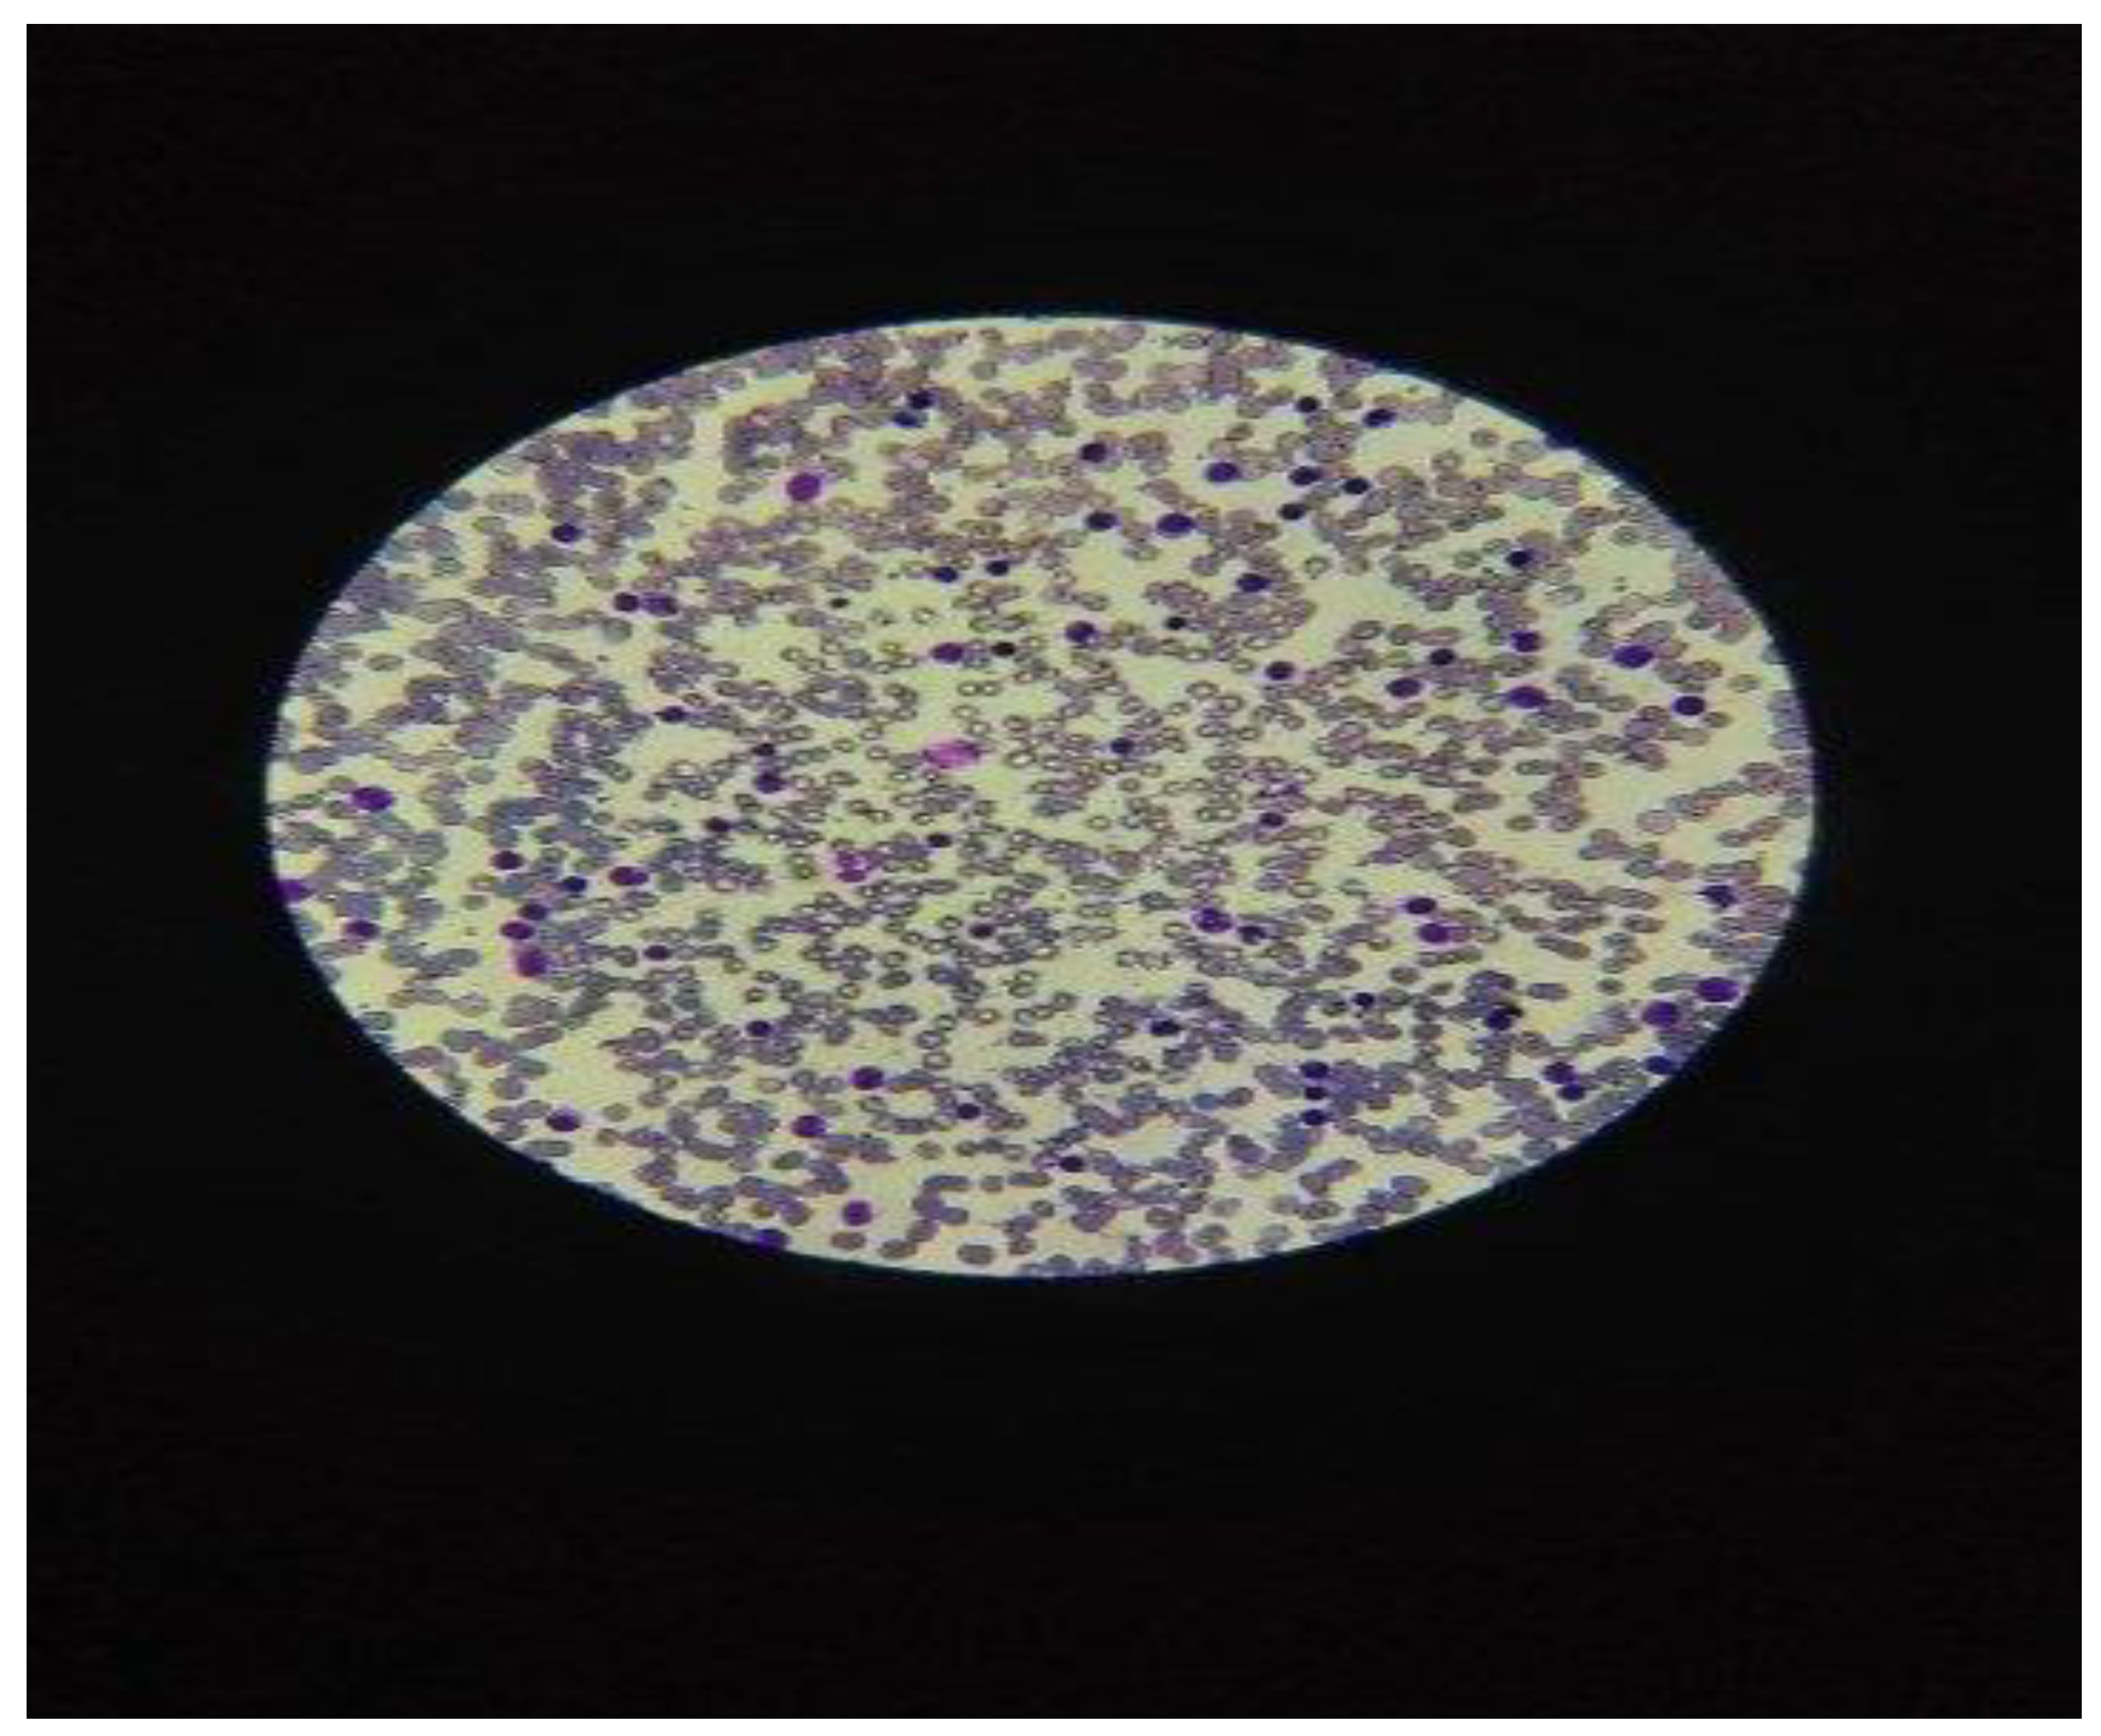

In the diagnosis of CLL and clinical staging were used the criteria recommended by the International Workshop on CLL, [6]. The patients underwent the evaluation in a complete physical exam for the diagnosis of chronic lymphocytic leukemia-type B, (CLL-B), which presented symptoms such as frequent cough, night sweats and retrosternal pain. The diagnosis of CLL was prior established by the cytologic exam of a blood smear from peripheral blood, in microscopy exam, with> 5000 lymphocytes in absolute value and less than 10% prolymphocytes in the hemogram with 5 Differential count, (CBC), [Figure 2].

Figure 2. Image of the microscopic smear in Chronic Lymphocytic Leukemia: numerous lymphocytes presenting a nucleus with an irregular contour, arranged in isolation on the peripheral blood slide and frequence relative of nuclear shadows Gumprecht.